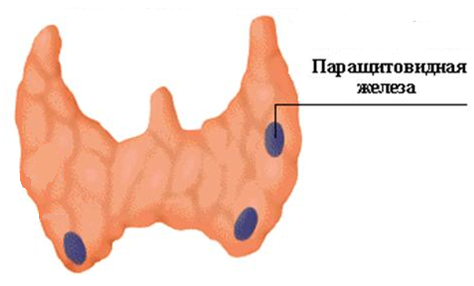

Иллюстрации и схемы по остеопорозу и паращитовидной железе